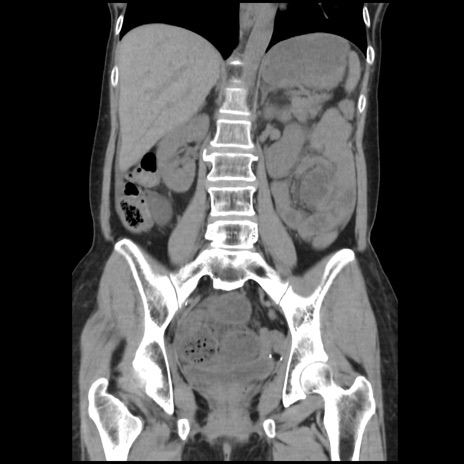

症例32(冠状断像)

【症例】40歳代 女性

【主訴】上腹部痛、嘔気・嘔吐

【現病歴】約9時間前頃から急に上腹部痛、嘔気、嘔吐が出現。改善しないため救急要請。

【既往歴】子宮頚癌(広汎子宮全摘術、放射線療法)、腸閉塞

【身体所見】腹部:平坦、軟、腸雑音亢進、上腹部を中心に腹部全体に圧痛あり。

【データ】WBC 8400、CRP 0.03